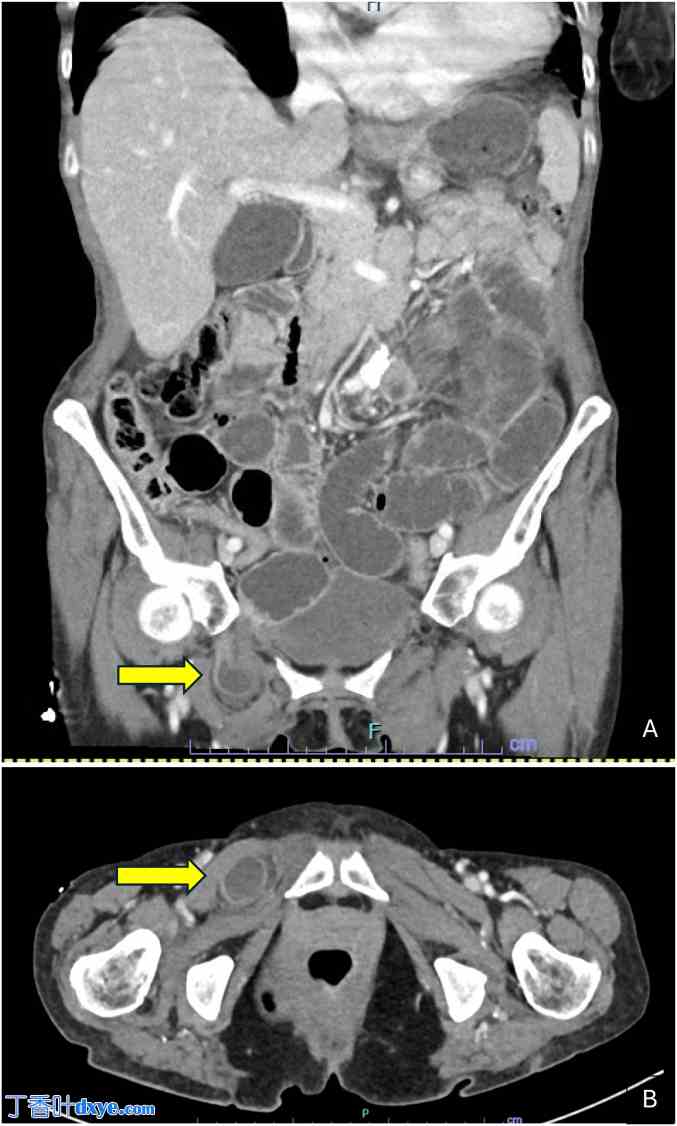

临床上,她表现为极度消瘦和虚弱,生命体征正常。右下腹有压痛。可见既往剖宫产留下的Pfannenstiel切口瘢痕,但腹部未触及肿块。右膝关节触痛明显,活动范围受限。但无肿胀、红斑或发热。初步实验室血液检查显示白细胞计数升高至21.5 × 10⁹/L,血小板计数为500/μL,C反应蛋白水平正常,为3 mg/L。最初安排了右膝关节X线检查,但未发现异常。随后进行了腹部和盆腔增强CT检查,证实为嵌顿性右侧闭孔疝引起的小肠梗阻。未见小肠受压的影像学表现(图1)。

图 1.

(A) 冠状位 CT 图像显示一段嵌顿的肠袢延伸至右侧闭孔管内,导致梗阻,近端小肠扩张即为佐证。(B) 轴位 CT 图像显示嵌顿的小肠袢位于耻骨肌和闭孔外肌之间。箭头指示闭孔疝的位置。